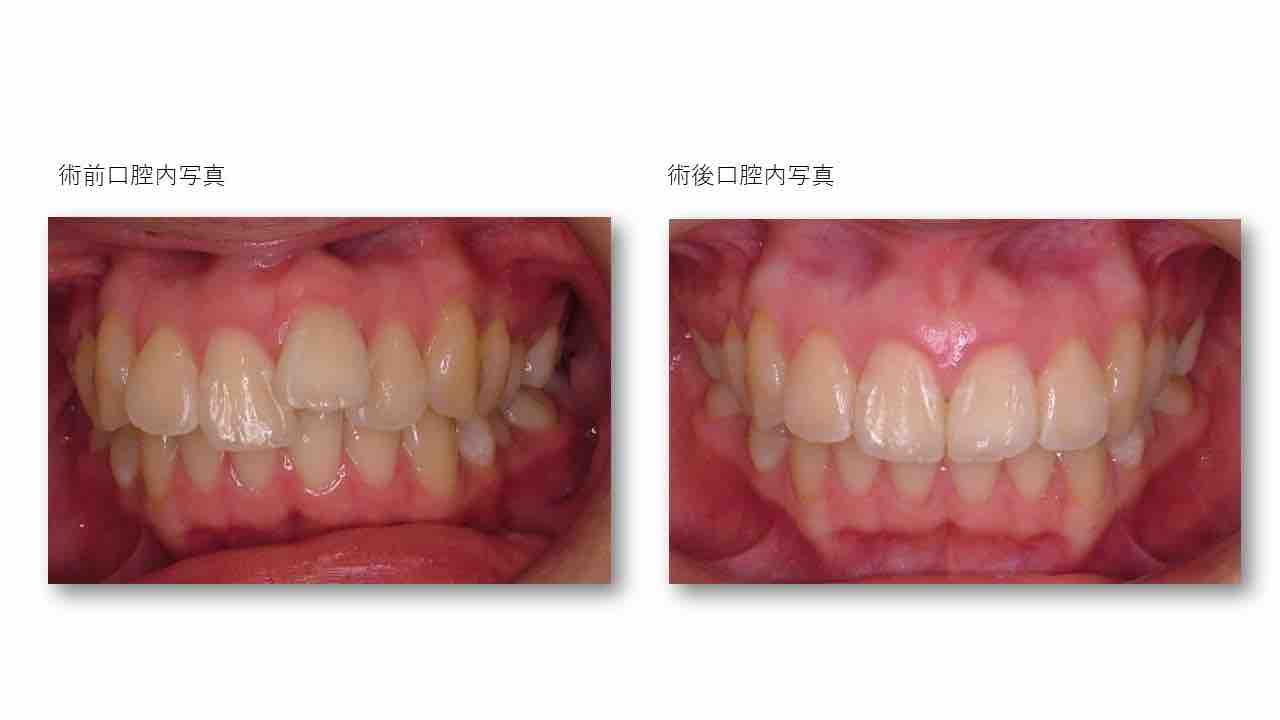

Èþ¤·¤¤¸ý¸µ¤Ë¡¡Ã°Ìî»õ²Ê¶ºÀµ¼£ÎŪ

Èþ¤·¤¤¸ý¸µ¤Ë¡¡Ã°Ìî»õ²Ê¶ºÀµ¼£ÎÅ©

Èþ¤·¤¤¸ý¸µ¤Ë¡¡Ã°Ìî»õ²Ê¶ºÀµ¼£ÎŨ

Èþ¤·¤¤¸ý¸µ¤Î¡¡Ã°Ìî»õ²Ê¶ºÀµ¼£Îŧ

Èþ¤·¤¤¸ý¸µ¤Ë¡¡Ã°Ìî»õ²Ê¶ºÀµ¼£ÎŦ

Èþ¤·¤¤¸ý¸µ¤Ë¡¡Ã°Ìî»õ²Ê¶ºÀµ¼£ÎÅ¥

Èþ¤·¤¤¸ý¸µ¤Ë¡¡Ã°Ìî»õ²Ê¶ºÀµ¼£ÎŤ

Èþ¤·¤¤¸ý¸µ¤Ë¡¡Ã°Ìî»õ²Ê¶ºÀµ¼£ÎÅ£

Èþ¤·¤¤¸ý¸µ¤Ë¡¡Ã°Ìî»õ²Ê¶ºÀµ¼£ÎÅ¢

Èþ¤·¤¤¸ý¸µ¤Ë¡¡Ã°Ìî»õ²Ê¶ºÀµ¼£ÎÅ¡